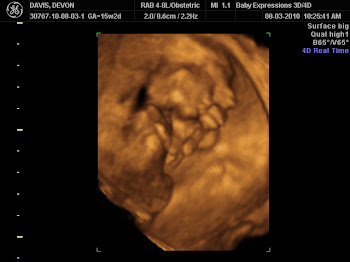

On Aug 3rd i went to a local 3D/4D Ultrasound place, just for fun and to see if i could find out if the baby was a boy or a girl. Well she was very stubborn and turned to face my back but completely adorable when we saw her pretty little face for a few seconds. And of course her hiney is cute to. I kept seeing something on her tummy but figured if something was wrong she would have said something, turns out she couldnt she isnt allowed to diagnose. The lady that runs the place got on the phone right away to my OB, she told him that during my exam she saw a defect and sent him a disc of my pictures. The dr's office called me on Aug 4th and told me that something was found and i needed to come in the next morning during walk in. They said that i may have to see maternal fetal medicine which is the high risk dr's for problems i knew then that something was very wrong and i was scared to death.